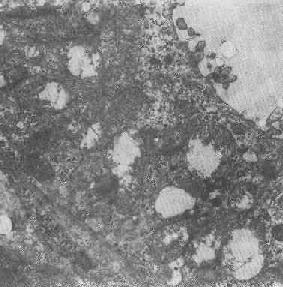

心肌细胞线粒体

图1-8 心肌细胞线粒体

线粒体为线状、长杆状、卵圆形或圆形小体,外被双层界膜。外界膜平滑,内界膜则折成长短不等的嵴并附有基粒。内外界膜之间为线粒体的外室,与嵴内隙相连,内界膜内侧为内室(基质室)(图1-8)。在合成甾类激素的内分泌细胞(如肾上腺皮质细胞、卵甾滤泡细胞、睾丸的Leydig细胞等),线粒体嵴呈小管状。内外界膜的通透性不同,外界膜的通透性高,可容许多种物质通过,而内界膜则构成明显的通透屏障,使一些物质如蔗糖和NADH全然不能通过,而其他物质如Na+ 和Ca 2+等也只有借助于主动运输才能通过。线粒体的基质含有电子致密的无结构颗粒(基质颗粒),与二价阳离子如Ca2+及Mg2+具有高度亲和力。基质中进行着β氧化、氧化脱羧、枸橼酸循环以及尿素循环等过程。在线粒体的外界膜内含有单胺氧化酶以及糖和脂质代谢的各种转移酶;在内界膜上则为呼吸链和氧化磷酸化的酶类。